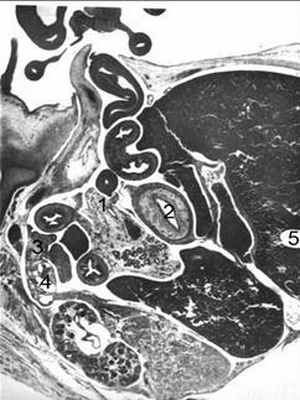

Несколько каудальнее поджелудочной железы размещаются петли тонкой кишки с просветом звездчатой формы (рис.1) .

Рис. 1. Сагиттальный срез плода 25мм длины:

1 - каудальный отдел кишечной петли, из которого формируется закладка сигмовидной кишки;

2 - закладка желудка и петли тонкой кишки;

3,4 - половая железа и первичная почка;

5 - правая и левая доли печени.

Микрофотосъемка: ув. 75

Между желудком, петлей тонкой кишки лежит каудальный отдел кишечной «петли» (толстой кишки). Ее брыжейка относительно тонка в начальной части, несколько расширена в конечном отделе и непосредственно переходит в общую. Установлено, что на данной стадии развития, на уровне верхнего края тела III поясничного позвонка от брюшной аорты отделяется короткий артериальный ствол, следующий вентрально и несколько краниальнее поджелудочной железы и представляющий собой закладку верхней брыжеечной артерии. Каудальнее первой ветви от переднебоковой стенки аорты под углом 130-140 о по отношению к ней отходит относительно длинный узкий ствол. Он проникает в общую брыжейку и выявляется между закладками прямой кишки, поджелудочной железы и двумя петлями тонкой кишки. Закладка нижней брыжеечной артерии отходит под прямым углом от брюшного отдела аорты.